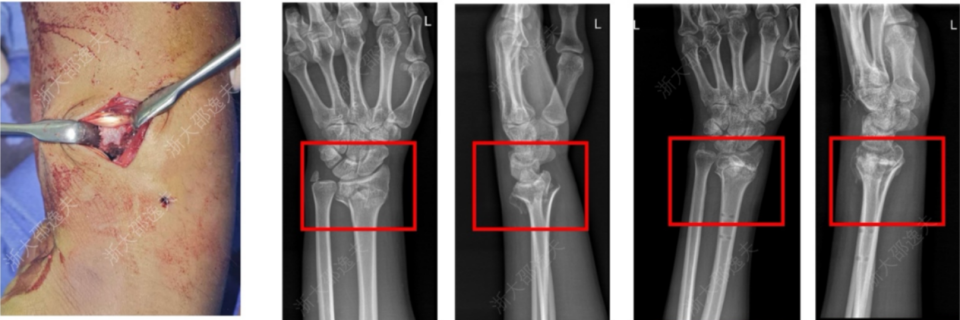

它在多家医院150余例受试病例中展现出了良好的安全性和有效性,各项指标达到预设标准。其中一位年轻工人因外伤致腕部粉碎性骨折,为避免传统的钢板内固定手术方案,医生通过一个2-3厘米的微创切口注入了“骨02”,便黏合了碎骨。术后复查显示,患者骨折愈合良好,手腕功能得以恢复。

来源:见水印